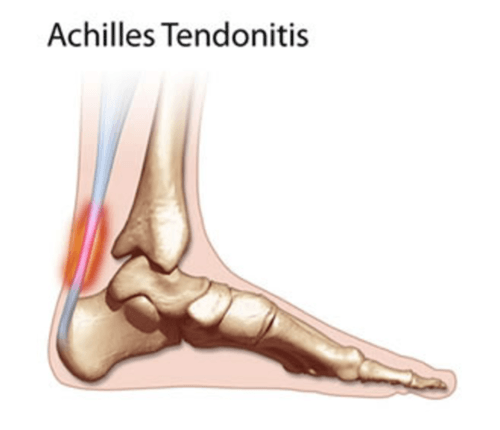

Achilles Tendonitis Treatment Bondi Junction, Barangaroo (Sydney CBD …

Achilles tendinitis – Mayo Clinic

Inflammation Of Achilles Tendon Cheapest Dealers, Save 65% | jlcatj.gob.mx

Achilles Tendonitis – Berry Physiotherapy | Mobile Physiotherapy Toronto

Achilles Tendonitis Basics | Florida Orthopaedic Institute

Achilles Tendinitis Info | Florida Orthopaedic Institute

Achilles Tendonitis Basics | Florida Orthopaedic Institute

Do You Have Achilles Tendonitis? – Mind & Body Chiropractic

Achilles Tendinitis – Procare Podiatric Medicine & Surgery

Achilles Tendinitis: Causes, Picture, Symptoms And Treatment

Achilles Tendonitis Causes, Symptoms & Treatment

Foot & Ankle Rehab Clinic | Nedlands – Achilles Tendonitis

Achilles Tendonitis Treatment in Sydney | Heel Clinic

Achilles Tendinitis – OrthoInfo – AAOS

Achilles Tendonitis / Tendonosis

Achilles Tendonitis: Causes, Treatment, and Prevention | Point Performance

Achilles tendinitis | Achilles tendonitis, Achilles tendonitis …